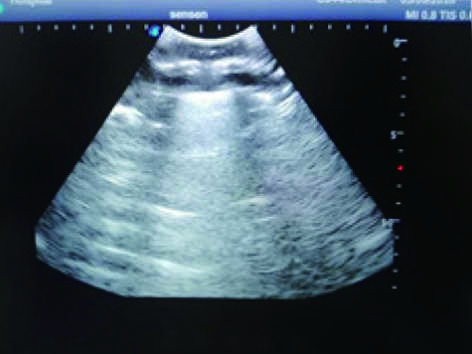

Thoracentesis Ultrasound Training Model

This model is an ideal choice for ultrasound-guided thoracentesis training with true-to-life skin feel and touch, accurate anatomical structures as well as real clinical ultrasound images. Realistic resistance to needle tips and correct landmarks provide excellent hands-on experience.

2)  Real clinical ultrasound images with clear muscles, connective tissues, lungs and pleural structures